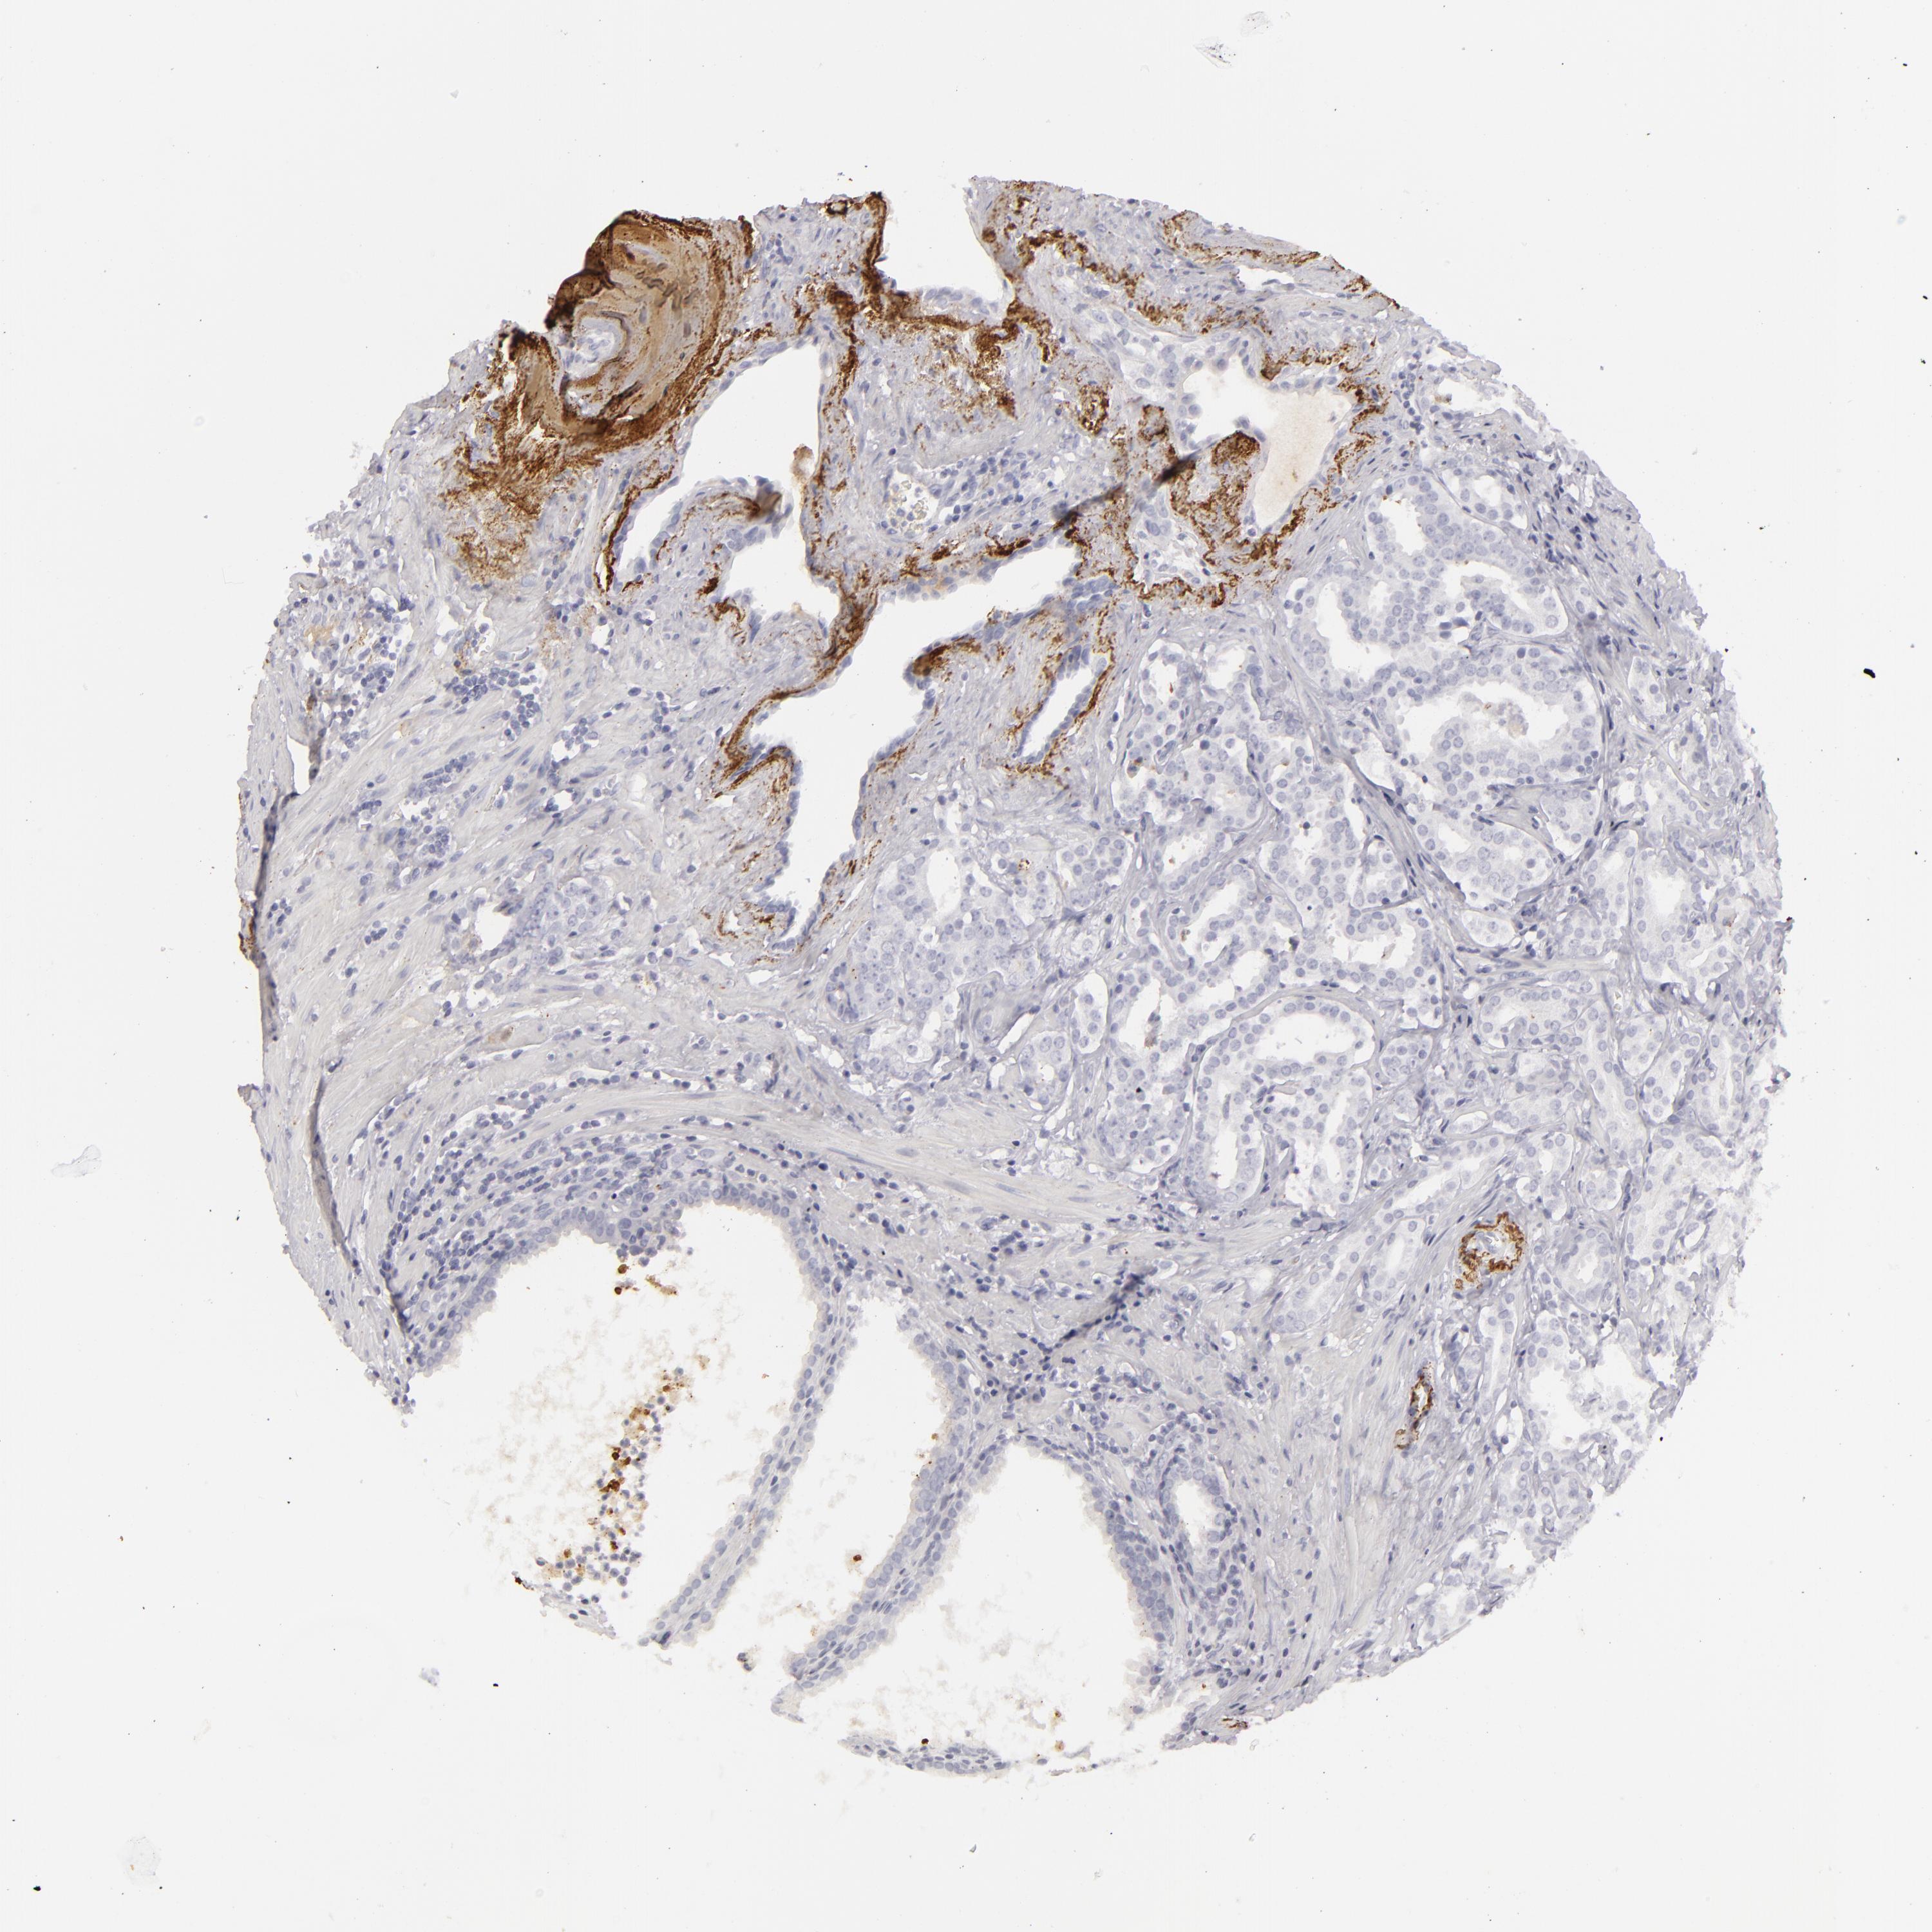

PROSTATE CANCER - Protein expressioni

A mouse-over function shows sample information and annotation data. Click on an image to view it in a full screen mode. Samples can be filtered based on level of antibody staining by selecting one or several of the following categories: high, medium, low and not detected. The assay and annotation is described here.

Note that samples used for immunohistochemistry by the Human Protein Atlas do not correspond to samples in the TCGA dataset.

Antibody stainingi

Antibody staining in the annotated cell types in the current human tissue is reported as not detected, low, medium, or high, based on conventional immunohistochemistry profiling in selected tissues. This score is based on the combination of the staining intensity and fraction of stained cells.

Each image is clickable and will lead to virtual microscopy that enables deeper exploration of all samples and also displays staining intensity scores, fraction scores and subcellular localization as well as patient and tissue information for each sample.

Antibody HPA029577

Antibody CAB002151

Adenocarcinoma, High grade

Adenocarcinoma, Low grade

Adenocarcinoma, Medium grade